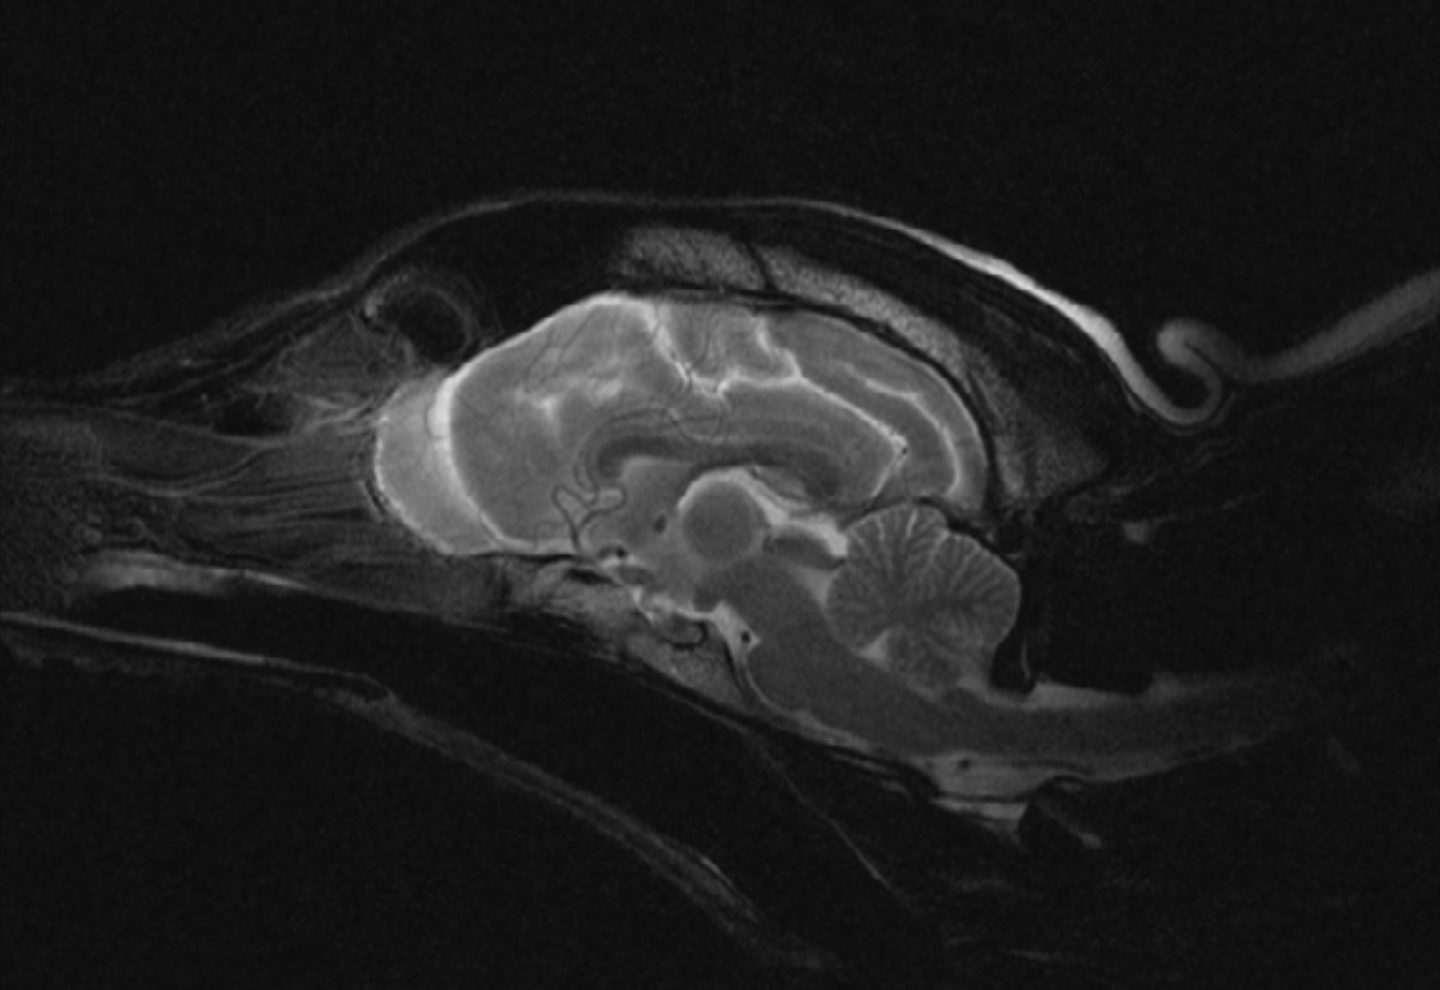

Die klinisch neurologische Untersuchung hat neben der gründlichen Allgemeinuntersuchung einen zentralen Stellenwert. Hierbei können mit geringem Aufwand die meisten zentralen Läsionen angesprochen werden. Weitergehende Untersuchungen beinhalten Blutuntersuchungen, eine Harnanalyse, eine Untersuchung des

Hirnwassers und eine Kernspintomographische Untersuchung des Gehirns. Bei Patienten mit erblicher Epilepsie wird man in allen Untersuchungsverfahren normale Befunde erhalten (Ausschlussdiagnostik). Die Erweiterung der Diagnostik um ein EEG (Hirnstrommessung) kann als einziges Nachweisverfahren bei diesen